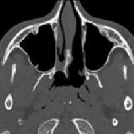

Neusbijholtenontsteking

Aan de twee neusgangen grenzen neusbijholten. Bij slechte doorgankelijkheid van deze neusgangen naar de neusbijholten kan het bekledende slijmvlies van de neusbijholten ontsteken.